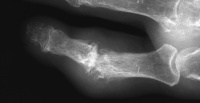

| Case 1. Large tophi have develped

about the right ulnar head and the left ulnar metacarpus, involving the

extensor tendons to the small finger. |